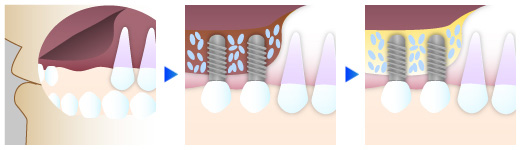

骨量が足りない場合には骨造成法による骨の再生をご提案します

歯を失った部分の顎骨は、時間と共に少しずつ退縮していきます。そのため、歯の欠損期間が長い場合には、インプラントを埋入するために必要な骨量が不足していることがあります。そのような場合には、インプラント治療ができるよう骨造成法による骨の再生をご提案いたします。

サイナスリフト

上顎のインプラント治療の際、骨の厚みが5㎜以下の場合に行う骨造成法です。歯茎を切開して、上顎洞を押し上げた場所に骨充填材を設置し、骨の再生を促します。

CGF

インプラント治療の際、骨や歯周組織の再生が必要な場合にはCGF治療を実施致します。患者さま自身の血液から生成するCGF(成長因子)を使用することで、拒絶反応などの心配なく、顎骨や歯周組織の再生が可能となります。